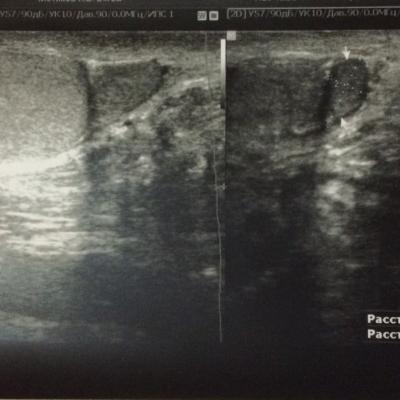

Аденома придатка левого яичка

Около года назад появились сильное боли в придатке левого яичка, при пальпации обнаружил плотное округлое образование, около 1 см. Последние 3 дня участились боли, колит и режет, отдает в левую ногу, боль при ходьбе. Прошел УЗИ. Насколько это опасно? Какой лечение, исход и прогноз ?

Злокачественные образования придатка яичка встречаются крайне редко. То, что описано на УЗИ может быть кистой, заполненной густой семенной жидкостью. Желательно переделать УЗИ в специализированном онкологическом или урологическом учреждении с выполнением допплерографии данного образования, чтобы выяснить его характер (кистозное или мягкотканное) и обратиться на прием к врачу-урологу или онкоурологу. Такие специалисты есть в и интервенционной радиологии им. Н.А. Лопаткина. Вы можете записаться на прием через Call-центр по телефону .